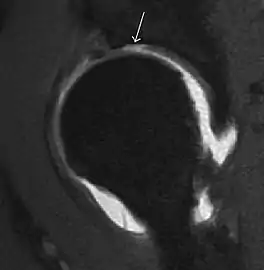

MRI has been shown to have 100% sensitivity and specificity in prospective studies of occult hip fractures. These fractures were diagnosed by bone marrow edema and a low signal fracture line, mainly on T1 or T2 weighted images (Figure 10).[1]

Figure 10:

Stress femoral neck fracture in a young athlete barely visible in X-ray film as a sclerotic line (arrow)[1]

In this case, Tc 99 scintigraphy shows a band of uptake[1]

Furthermore, T1 (left) and DP fat saturated (right) weighted MR images showed the fracture line and a pattern of edema.[1]